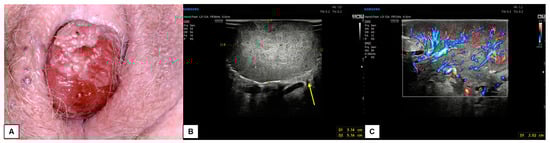

7.3. Malignant Vulvar Lesions

- Measurement from the adjacent most superficial dermal papilla to the deepest point of invasion

- Measurement from the basement membrane of the deepest adjacent dysplastic (tumor-free) rete ridge to the deepest point of invasion, which should be the technique of choice. Because epidermal ridges cannot be distinguished on ultrasonography, our suggestion is to take the lower hyperechogenic line of the epidermal layer as a reference (Figure 10).